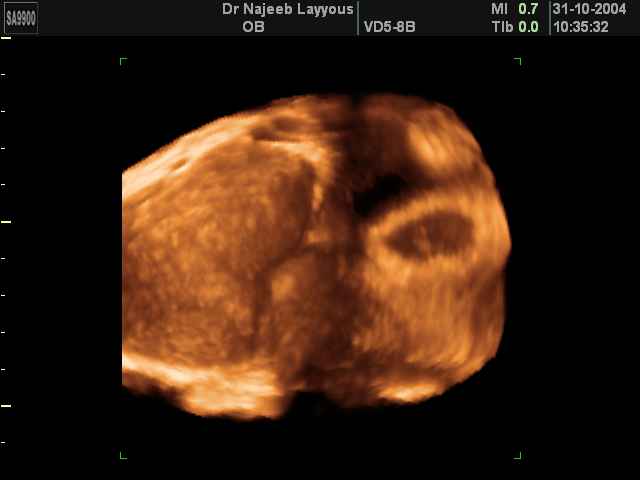

- لقطات فيديو للجنين بجهاز الموجات فوق صوتية رباعي الأبعاد

- صور جانبية لرأس الجنين

- صور طبية للحمل للأطباء